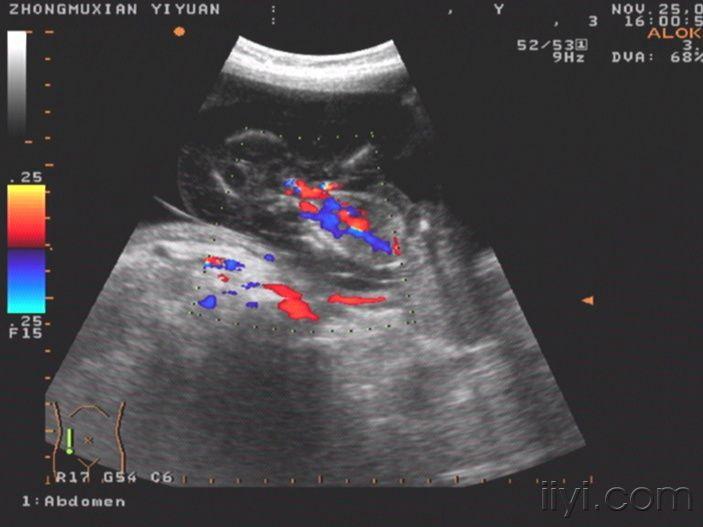

这个胎儿穿上了“太空衣”(典型胎儿水肿图片,值得分享!)

一位32岁经产妇,孕20周前来检查,发现胎儿被一层透明的膜状物包绕,从头颅到肢体,考虑胎儿水肿综合症!